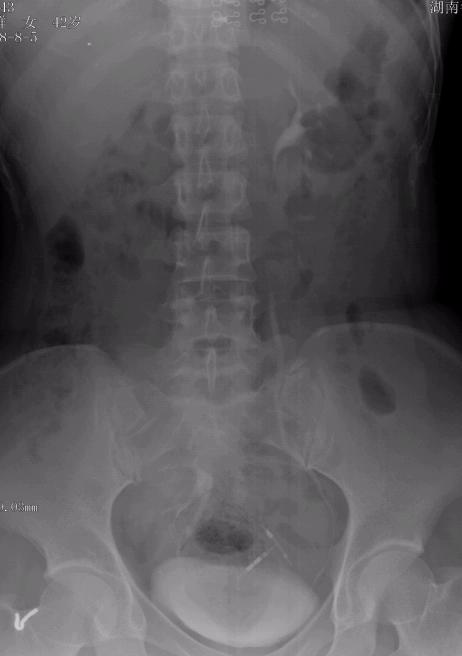

以下是引用杀毒软件在2008-8-27 20:11:00的发言:[br]右肾区未见右肾显影,膀胱右上方见右肾显影----未见明显输尿管显影--估计是过短[br][br]考虑---异位肾〔盆腔〕,楼主好运气,不多见病例。

以下是引用wangxingjian在2008-8-27 21:36:00的发言:[br]盆腔异位肾